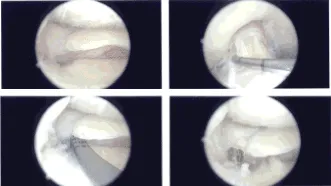

Once they were there, then the root was very well induced. The sutures were put into the tibia with the use of 4.75-mm SwiveLock and good tension was achieved, which was checked intraoperatively, and the pictures were taken and saved.

Intraoperative Arthroscopy Images